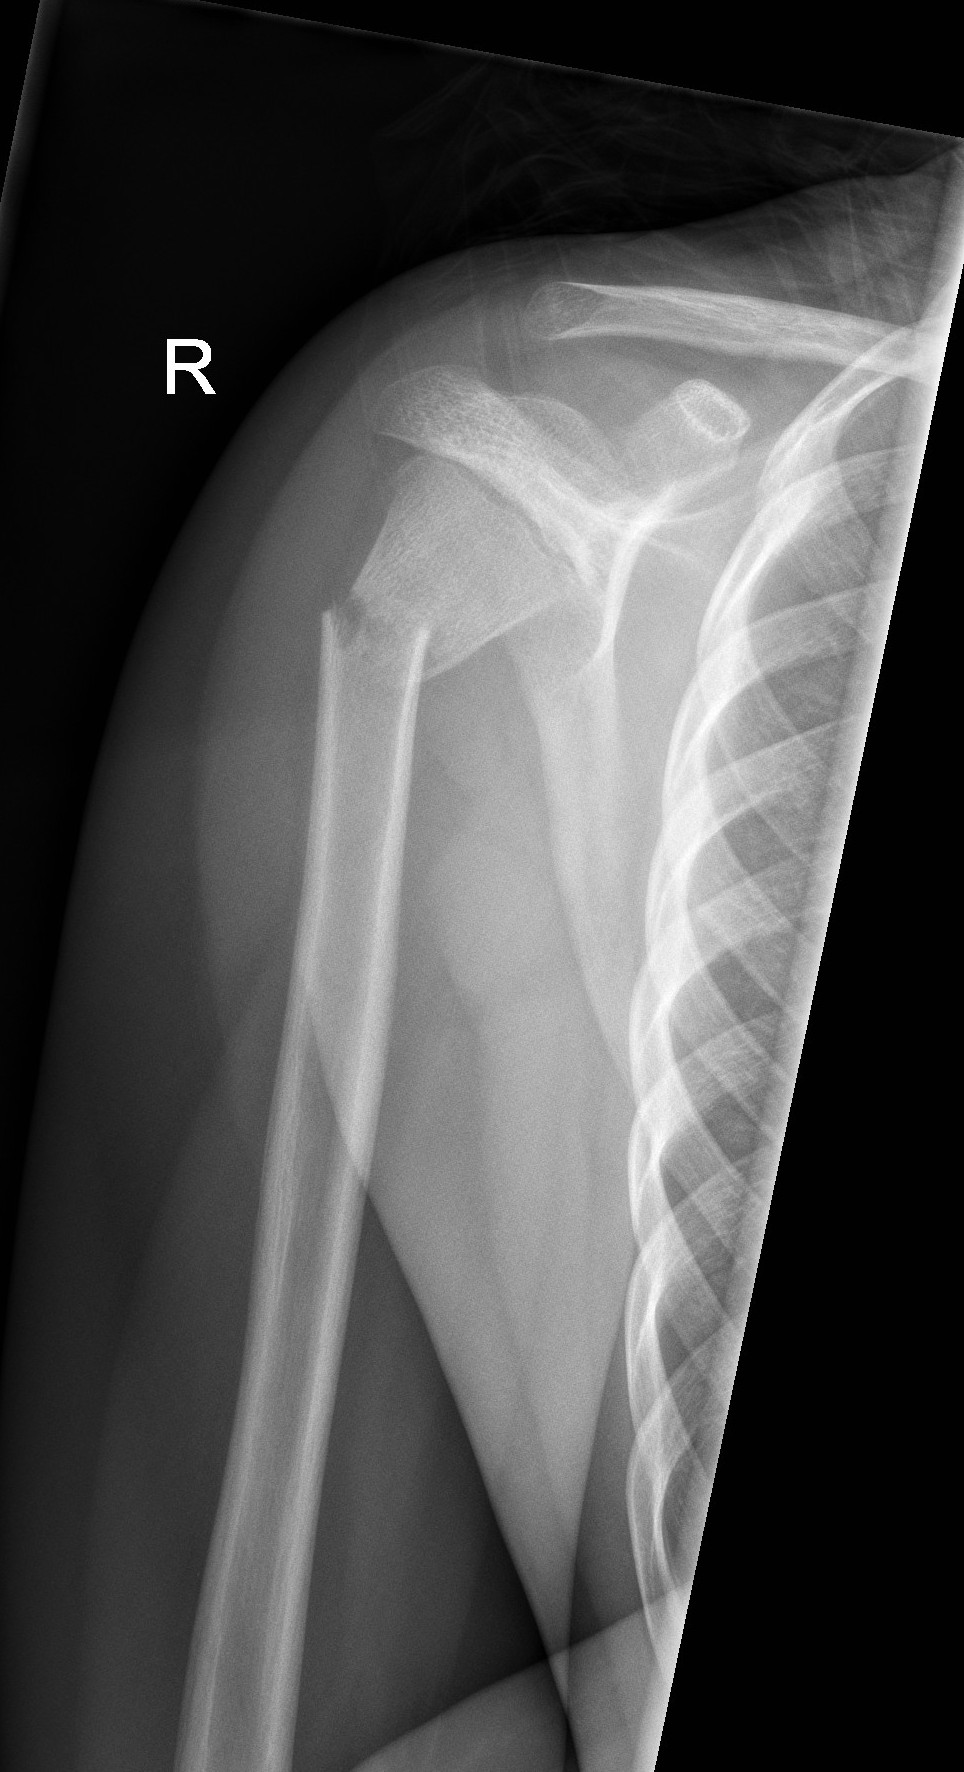

Proximal Humerus Fractures

- Younger children are prone to buckle fractures of the proximal humerus.

Above: Buckle fracture of proximal humerus